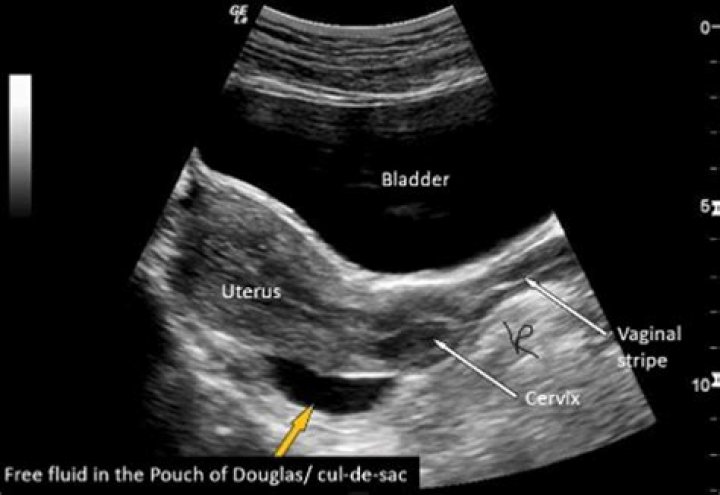

The Pouch of Douglas is an anatomical structure located in the female pelvis, specifically between the rectum and the posterior wall of the uterus. It is part of the peritoneal cavity and serves as a potential space that can accumulate fluid in certain pathological conditions. Understanding its location and function is essential for healthcare providers when interpreting ultrasound images.

• Forms the lowest point of the female peritoneal cavity

• Can accumulate fluid, blood, or pus in pathological conditions

This anatomical structure is named after Dr. James Douglas, a Scottish anatomist who first described it. Its position makes it a critical point of focus during pelvic ultrasound examinations, particularly in cases involving fluid accumulation or mass detection.